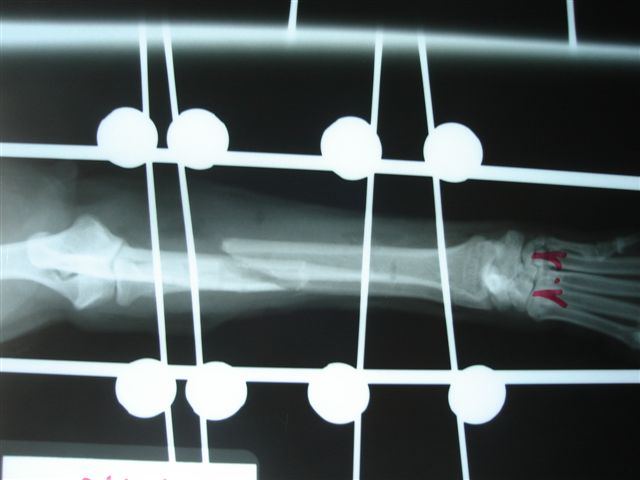

Fijación Externa en IVOT

Fijación Externa

IX CURSO BASICO DE FIJACION EXTERNA.

Casos prácticos alumnos.